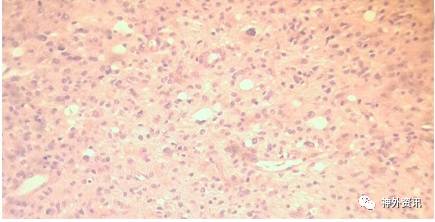

1994年,44岁的男性患者,因剧烈头痛伴左臂无力1月余就诊;头颅MRI成像显示右额后深部肿瘤(图1A),施行手术切除肿瘤。手术过程较为顺利,肿瘤标本的病理学诊断为多形性胶质母细胞瘤。术后患者接受全脑放疗和化疗。随访3周时发现左上肢无力症状消失。3月时头颅CT复查未见肿瘤复发。以后定期复查头颅MRI,均提示肿瘤未复发(图1B),直至2016年7月头颅MRI复查仍未见复发,而患者术后已存活22年。请3位神经病理学家复读病理组织切片,证实为典型的恶性胶质瘤。

图1. 患者术前与术后的头颅磁共振成像比较。A. 术前MRI显示肿瘤位于右额叶后部深处,增强扫描时呈强化灶,内有坏死区,周围脑组织水肿;B. 术后MRI复查未见肿瘤复发。

图2. 病理学检查结果。上图:HE染色示伴有微囊性变的胶质瘤多细胞簇,核仁明显,核有高度异型性。下图:A.GFAP免疫反应性强烈;B.免疫染色显示Ki-67增殖指数高。